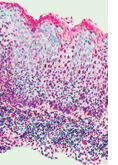

Histologisch stehen bei der vulvären intraepithelialen Neoplasie Zellreifungsstörungen mit Para- oder Dyskeratosen, Hyperchromasie der Zellkerne und eine Zunahme atypischer Mitosen im Vordergrund. Das Vorkommen von Koilozyten, atypischen, balloniert erscheinenden Plattenepithelzellen ist kennzeichnend für eine HPV-induzierte VIN.

Klassische VIN Aus histopathologischer Sicht lassen sich warzige, basaloide und gemischte Typen unterscheiden. Für den warzigen Typ ist ein kondylomatöses Erscheinungsbild charakteristisch. Häufig werden Koilozyten, mehrkernige Zellen, mitotische Anomalien und Akanthose vorgefunden. Beim basaloiden Typ ist das Epithel verdickt und die Oberfläche erscheint flach und nicht-papillomatös. Relativ einheitlich undifferenzierte basaloide Zellen durchsetzen die gesamte Epidermis. Gemischte warzig/basaloide Formen kommen oft in derselben Läsion vor.

Differenzierte VIN Kennzeichnend ist der hohe Grad der Differenzierung bei weitgehendem Erhalt der Gewebearchitektur. Das histologische Bild zeigt ein verdicktes Epithel mit Parakeratose. Immunhistochemisch wurde eine p53-Überexpression in differenziertem VIN (dVIN) nachgewiesen.